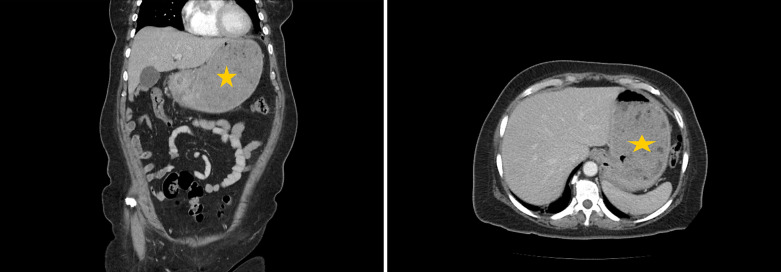

简介急性胃扩张(AGD)是由气体、胃分泌物或食物堆积引起的胃部大量膨胀。AGD 是一种放射学诊断,没有明确的发病机制,由于缺乏明确的诊断标准和医生的认识,AGD 经常被误诊:在本病例系列中,我们描述了 4 位 AGD 患者的临床表现和治疗结果。其中三名(75%)患者为女性,一名(25%)患者为男性。患者年龄从 53 岁到 84 岁不等,平均年龄为 73.5 岁。腹痛、恶心和呕吐是最常见的主诉。两名患者(50%)患有癌症,一名患者(25%)患有后天性十二指肠狭窄,第四名患者出现回肠梗阻:AGD是一种外科急症,死亡率高达50%-100%;因此,及时诊断和治疗至关重要。在此,我们描述了本院诊断和处理的一系列 AGD 病例。我们旨在提高人们对这一致命但未得到充分认识的临床实体的认识。

Introduction: Acute gastric dilatation (AGD) is a massive distension of the stomach caused by the accumulation of gas, gastric secretions, or food material. AGD is a radiological diagnosis with no clear etiopathogenesis and is often misdiagnosed owing to a lack of clear diagnostic criteria and physician awareness.

Case presentation: In this case series, we describe the clinical presentations and outcomes of 4 patients with AGD. Three (75%) of the patients were female, and one (25%) was male. The patients' ages ranged from 53 to 84 years, with an average age of 73.5 years. Abdominal pain, nausea, and vomiting were the most frequently reported complaints. Two (50%) patients had cancer, one (25%) had an acquired duodenal stenosis, and the fourth patient experienced an ileus.

Conclusion: AGD is a surgical emergency with a 50-100% mortality rate; thus, prompt diagnosis and management are crucial. Herein, we describe a case series of AGDs that were diagnosed and managed at our institution. We aim to raise awareness about this fatal yet underrecognized clinical entity.